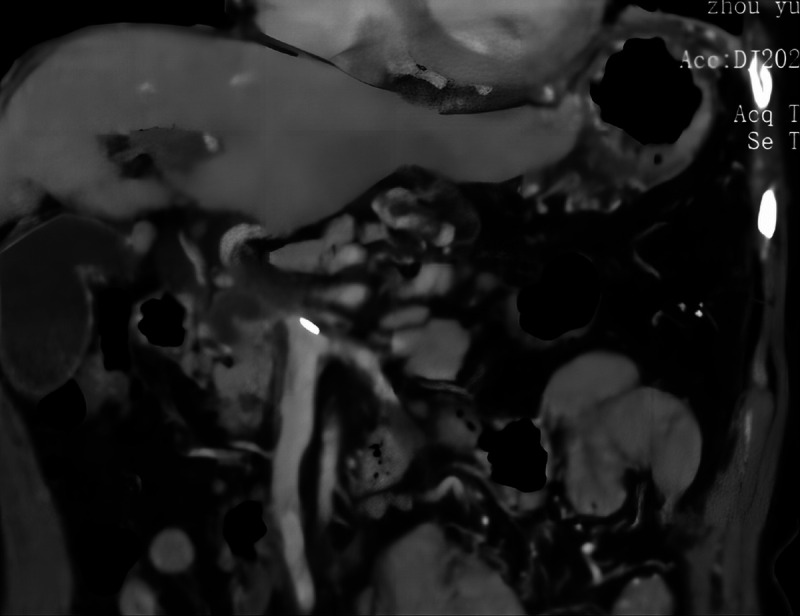

EUS-guided cyanoacrylate glue injection for the management of refractory bleeding from postglue ulcer following gastric varices treatment (with video).